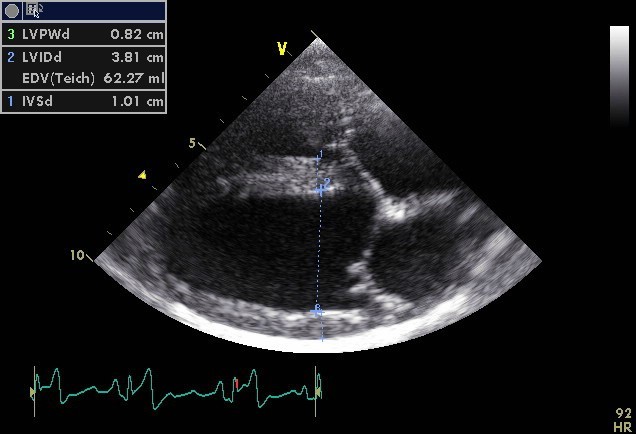

What does this show?

LV dimensions